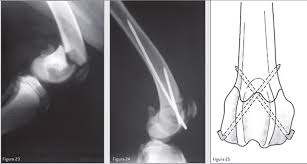

FRACTURA HELICOIDAL DE TERCIO PROXIMAL DE FÉMUR